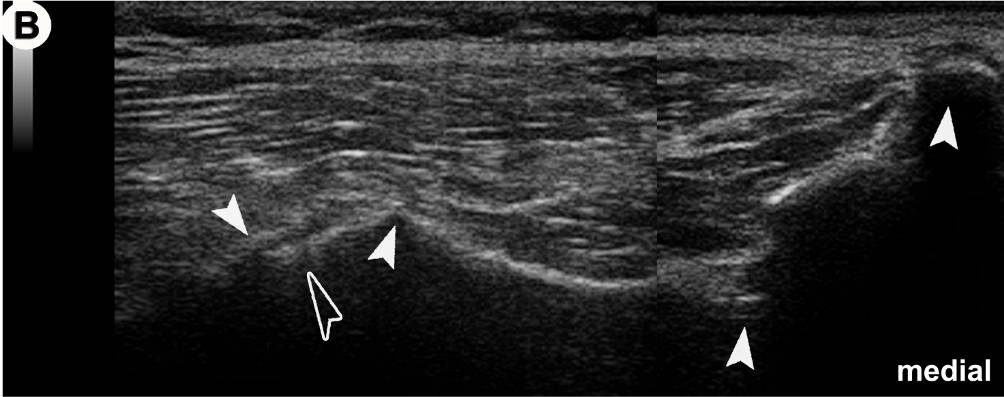

US-Darstellung und experimentelle Blockade (Pfeilköpfe: Nadel) des N. cutaneus femoris lateralis an einer Körperspenderin.  Mittlerweile gängige Anwendung in der Regionalanästhesie und Schmerztherapie